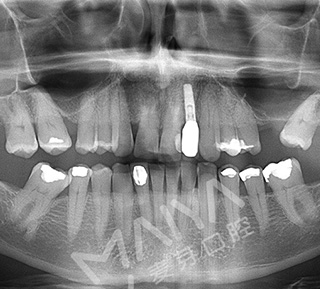

深圳市二院原口腔科主任、深圳麦芽口腔总院长、深圳科技进步一等奖获得者郑苍尚教授在仔细检查Jack的牙齿情况后,通过科学的德国卡瓦数字化口腔CT三维检测,指出Jack因为牙外伤后而导致牙反复发炎松动,牙CT显示牙槽骨严重缺损,不能一期种牙。

郑院长经过权威分析制定再次种植牙手术的种植方案,首先为Jack拔出患牙做了GPR植骨和保持位点手术,等四个月后缺牙部位形成很好的新骨,再次种牙。

四个月后的Jack再次来院,经过麦芽口腔团队的努力,成功为Jack种上了牙齿,恢复了原有牙列的完满形态,手术的成功使这位德国男子的笑容更加灿烂。